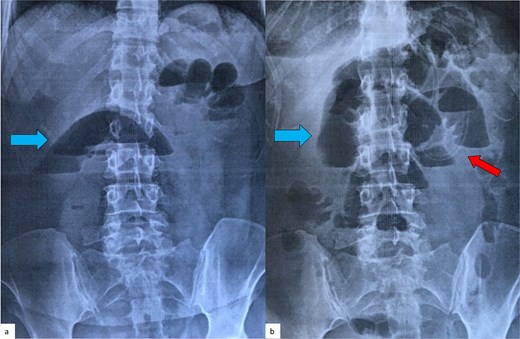

The first case involved a 48-year-old woman who arrived at the emergency department with vomitting and diffuse abdominal pain over the past 24 hours. Her medical and surgical histories were unremarkable. Laboratory tests showed an elevated white blood cell (WBC) count of 17.4 mm3/μl (normal range 4.3–10.3 mm3/μl), while the C-reactive protein (CRP) level was normal at 0.4 mg/dl (normal range < 0.5 mg/dl). A plain abdominal X-ray in the upright position demonstrated air-fluid levels typical of intestinal obstruction (Fig. 1a), whereas the ultrasound examination was inconclusive. A CT scan revealed distention of the small intestine from the duodenum to the terminal ileum without identifying the cause of the obstruction. Initially, a nasogastric tube was placed for conservative management. After 48 hours, the patient’s condition and plain abdominal imaging (Fig. 1b) showed no signs of improvement, leading to the decision for an exploratory laparotomy.

Plain abdominal radiograph of the patient (first case) in an upright position, on admission (a) and 48 hours later (b). Air-fluid levels (blue arrows), typical of small bowel obstruction, are clearly seen in both films, with no signs of improvement after conservative treatment with a nasogastric tube (red arrow).